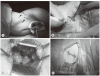

Figures